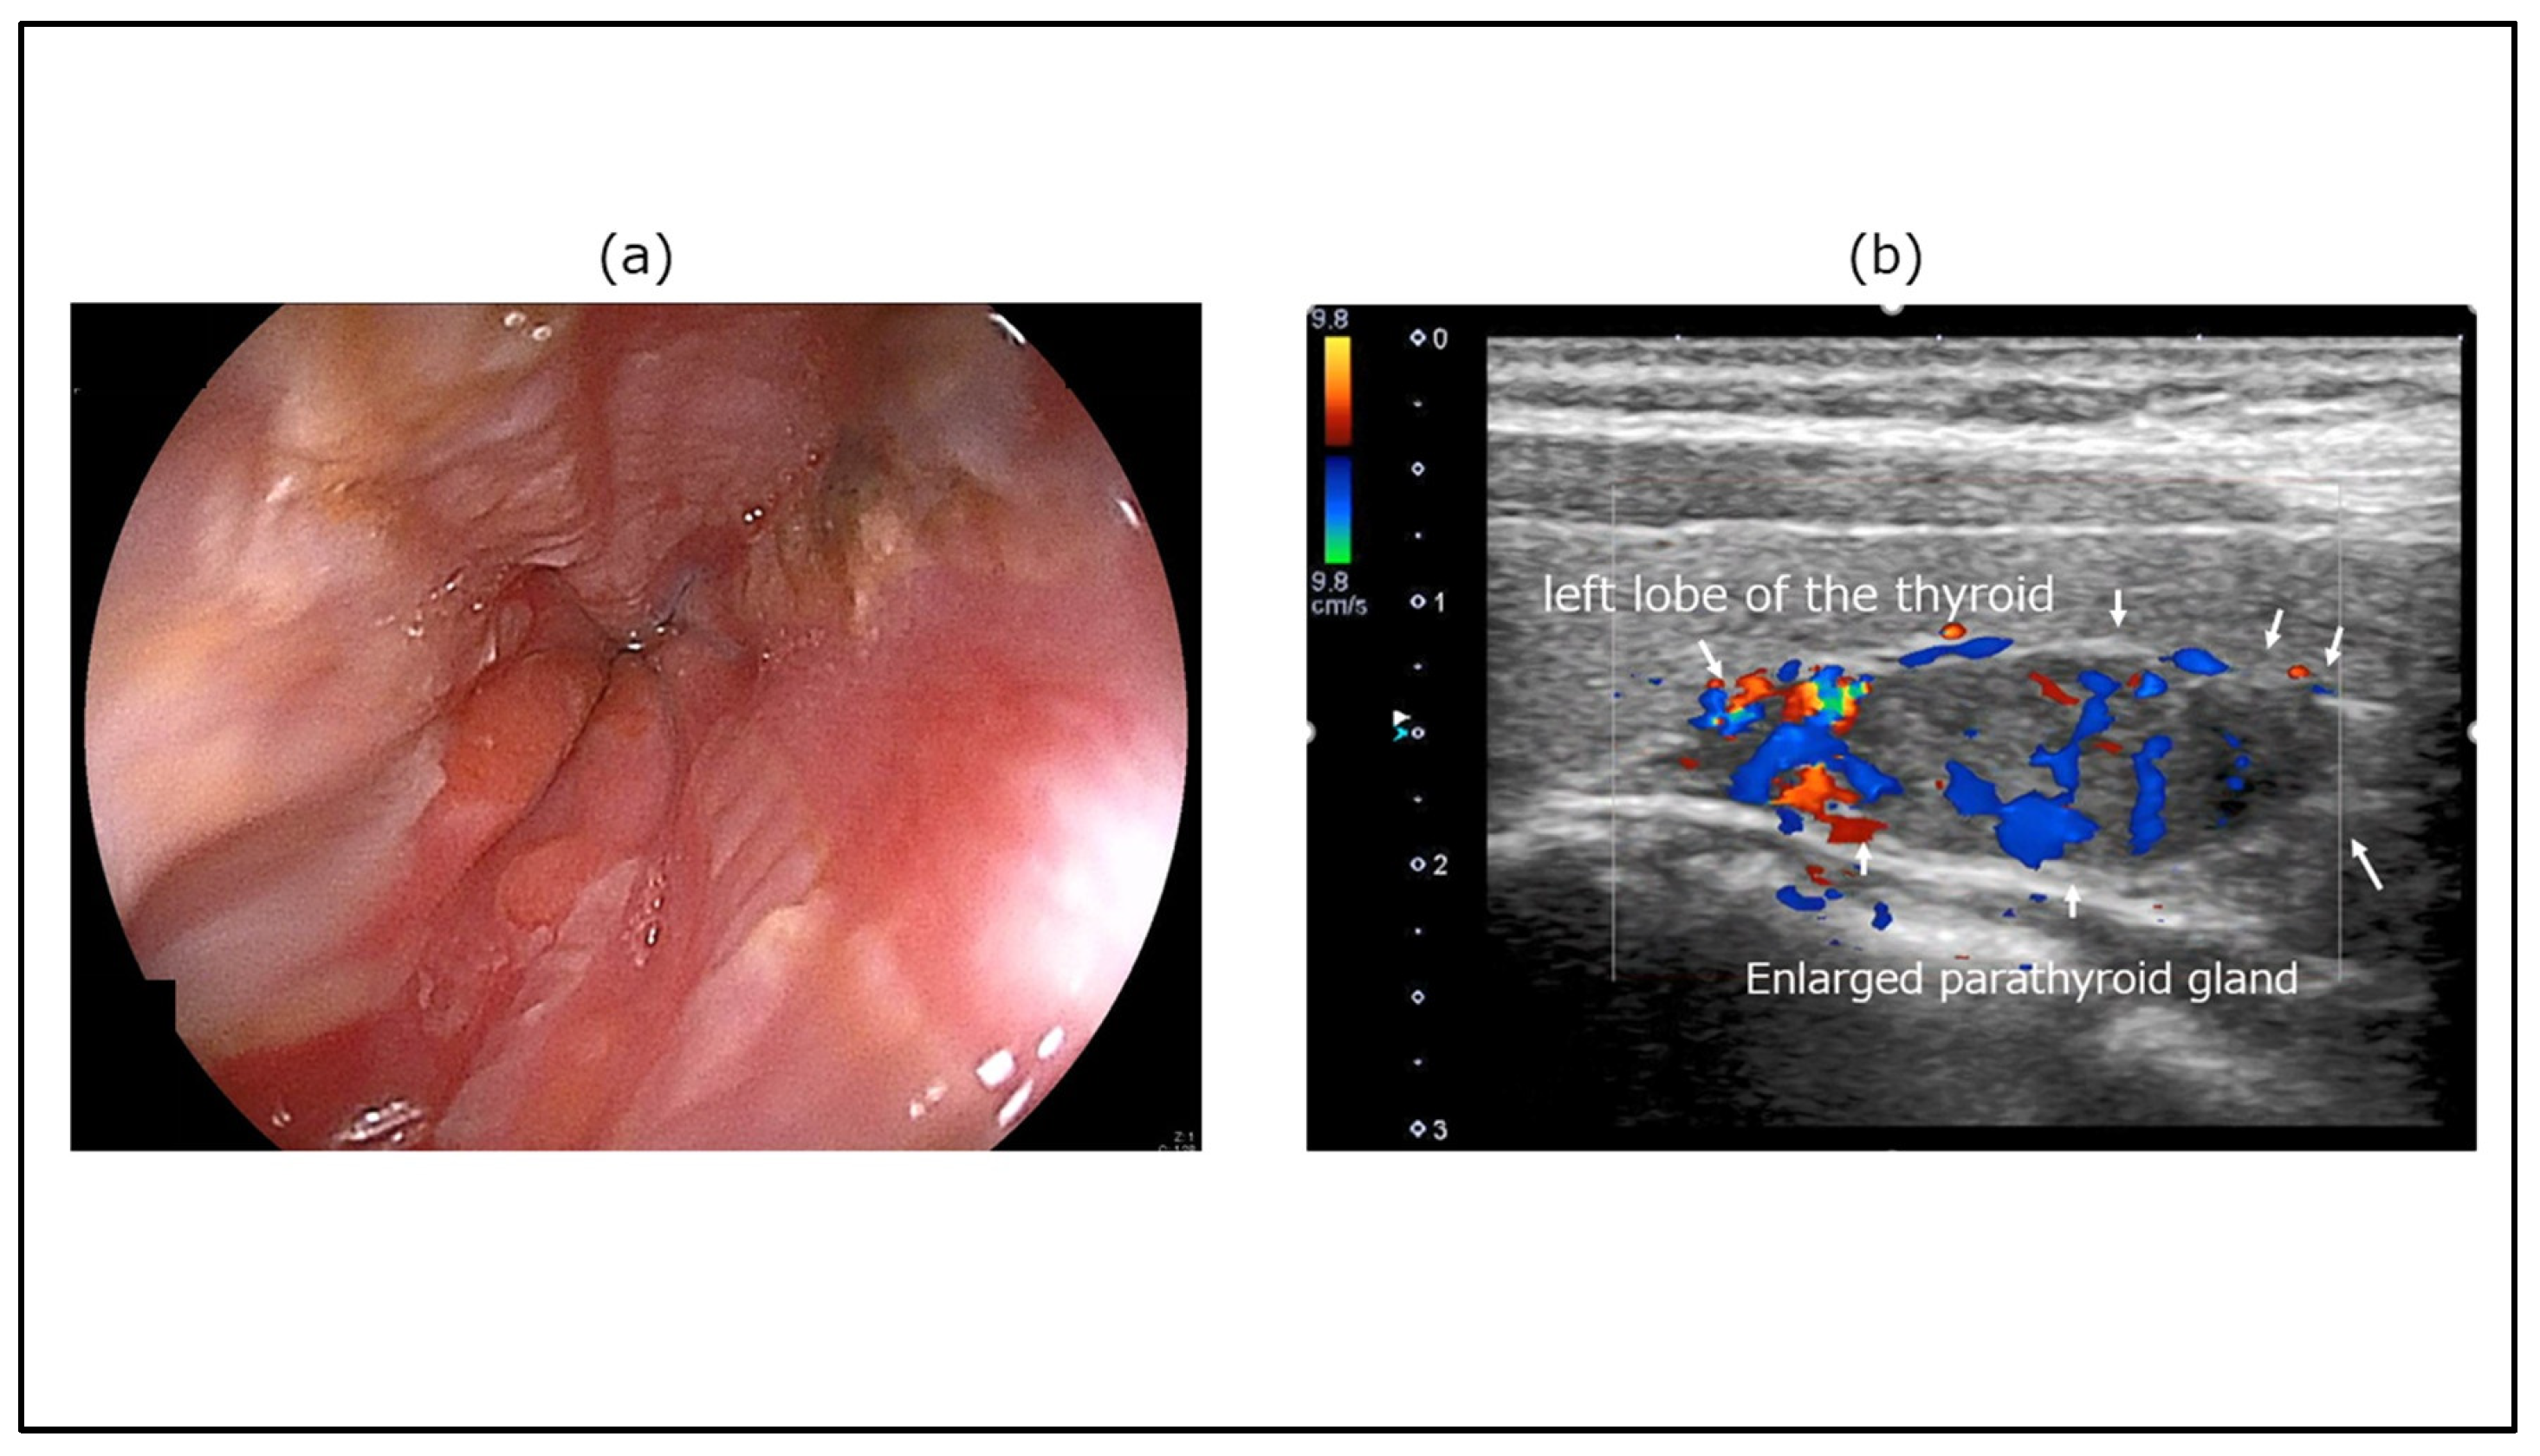

A patient presenting with secondary constipation in the context of an endocrine disorder is shown in Figure 5. Gastroesophageal reflux disease was found on an upper gastrointestinal endoscopic image of a 50-year-old woman who presented to our clinic with symptoms of upper abdominal pain, anorexia, and constipation. Ultrasonography (Aplio i700 TUS-I700; Canon Medical Systems, Otawara, Japan) revealed an enlarged parathyroid mass with abundant blood flow signals in the dorsal thyroid gland. Various tests indicated that the symptoms were the result of hypercalcemia caused by hyperparathyroidism associated with a parathyroid adenoma.

Figure 5. A case of secondary constipation in the context of endocrine disorders. (a) Upper gastrointestinal endoscopy image. Mucosal damage was observed in the esophagus. (b) TUS image (Aplio i700 TUS-I700; Canon Medical Systems, Otawara, Japan). Ultrasonography revealed an enlarged parathyroid mass with abundant blood flow signals in the dorsal thyroid gland. The enlarged parathyroid gland is indicated by arrows.